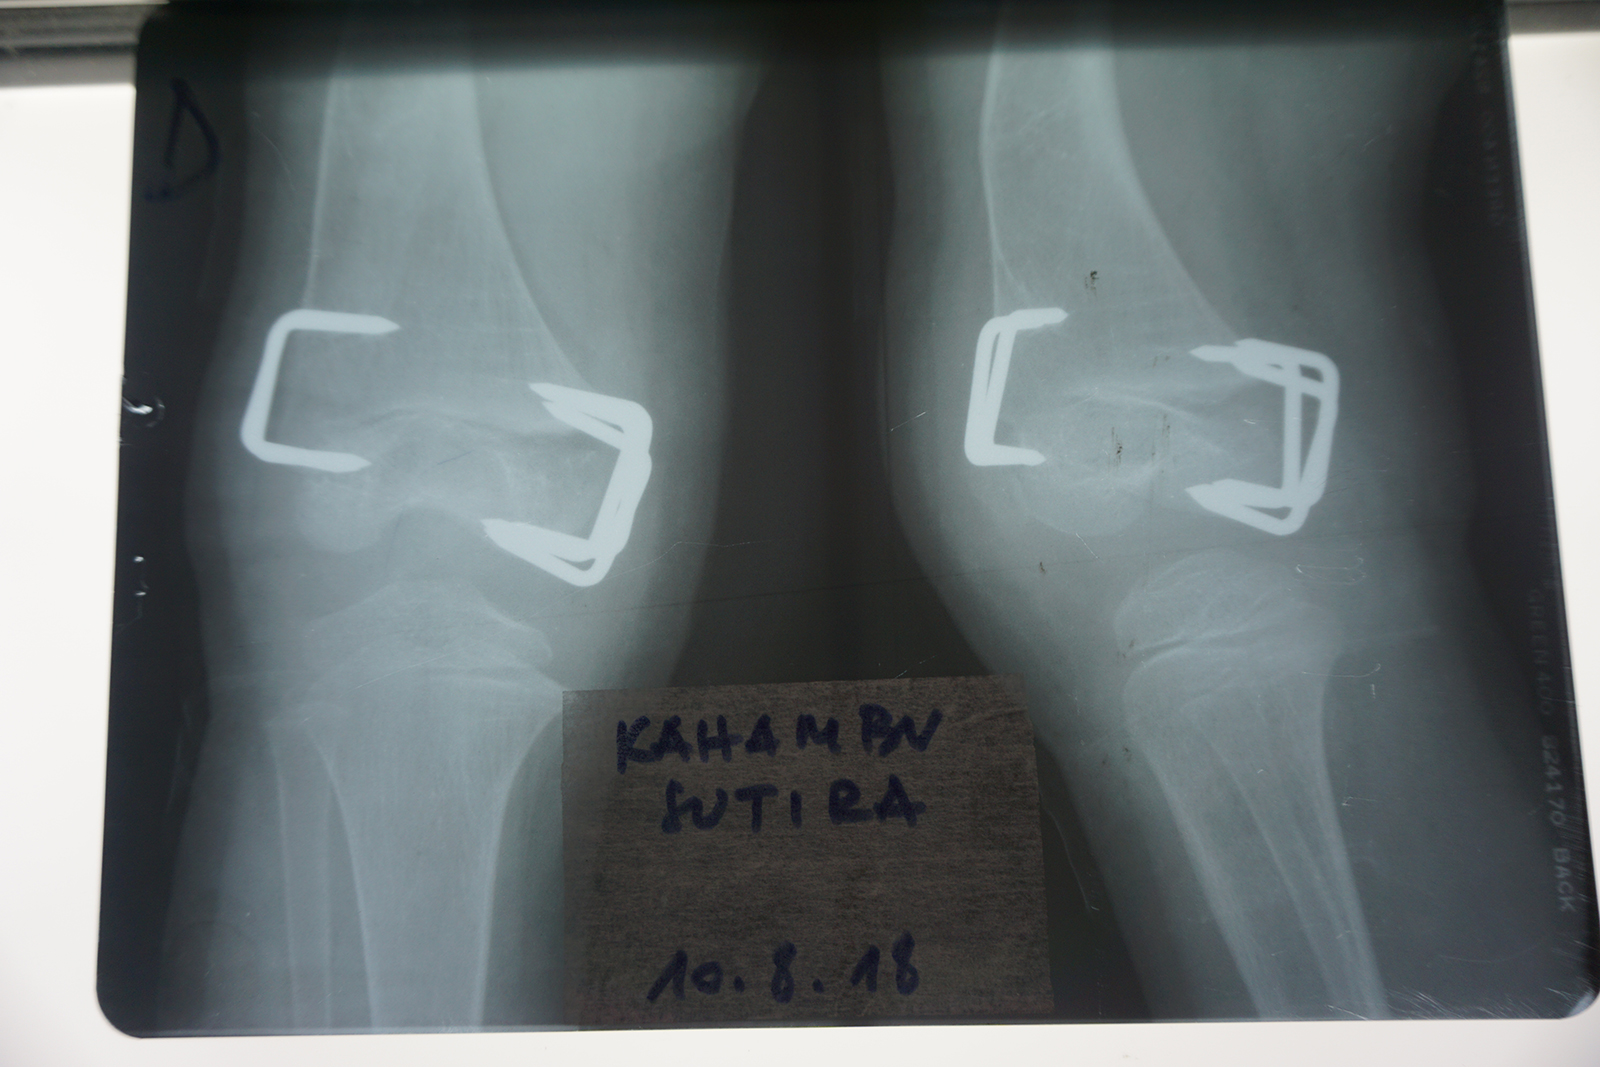

Wird das Wachstum auf einer Seite einer solchen Fuge gezielt gebremst, wächst der Knochen auf der gegenüberliegenden Seite weiter. Dadurch kann sich eine Achsfehlstellung über Monate oder Jahre allmählich selbst korrigieren. Die Wachstumshemmung erfolgt durch kleine Klammern oder Plättchen, die die Wachstumsfuge überbrücken und so deren Aktivität einschränken (Abb. 4).

Bei Arielle brachten wir im August 2017 Klammern an der Außenseite des rechten Kniegelenkes an, um die O-Bein-Stellung zu korrigieren (Abb. 5). Nach einigen Monaten war die Achsfehlstellung ausreichend ausgeglichen. Es blieb jedoch weiterhin die Überlänge des rechten Beines bestehen.

Um dieses Längenproblem zu behandeln, wurden im August 2018 zusätzlich Klammern an der Innenseite derselben Wachstumsfuge eingesetzt (Abb. 6). Dadurch wurde das Wachstum des rechten Beines insgesamt verlangsamt, ohne es vollständig zu stoppen. Andere Wachstumsfugen blieben weiterhin aktiv, jedoch wuchs das behandelte Bein nun langsamer als das unbehandelte linke. Auf diese Weise erhielt das linke Bein die Möglichkeit, im Wachstum aufzuholen.

Im November 2021 war schließlich eine gleiche Beinlänge erreicht. Ab März 2022 begann das linke Bein das rechte leicht zu überholen, sodass wir uns zur Entfernung der Klammern entschieden.

Klammern an der Außenseite des rechten Kniegelenkes, November 2017

Korrektur O-Bein-Stellung, November 2017